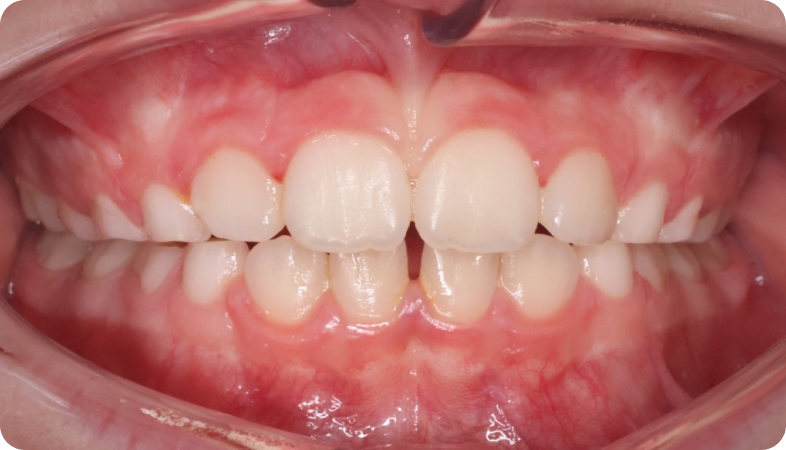

Cas cliniques